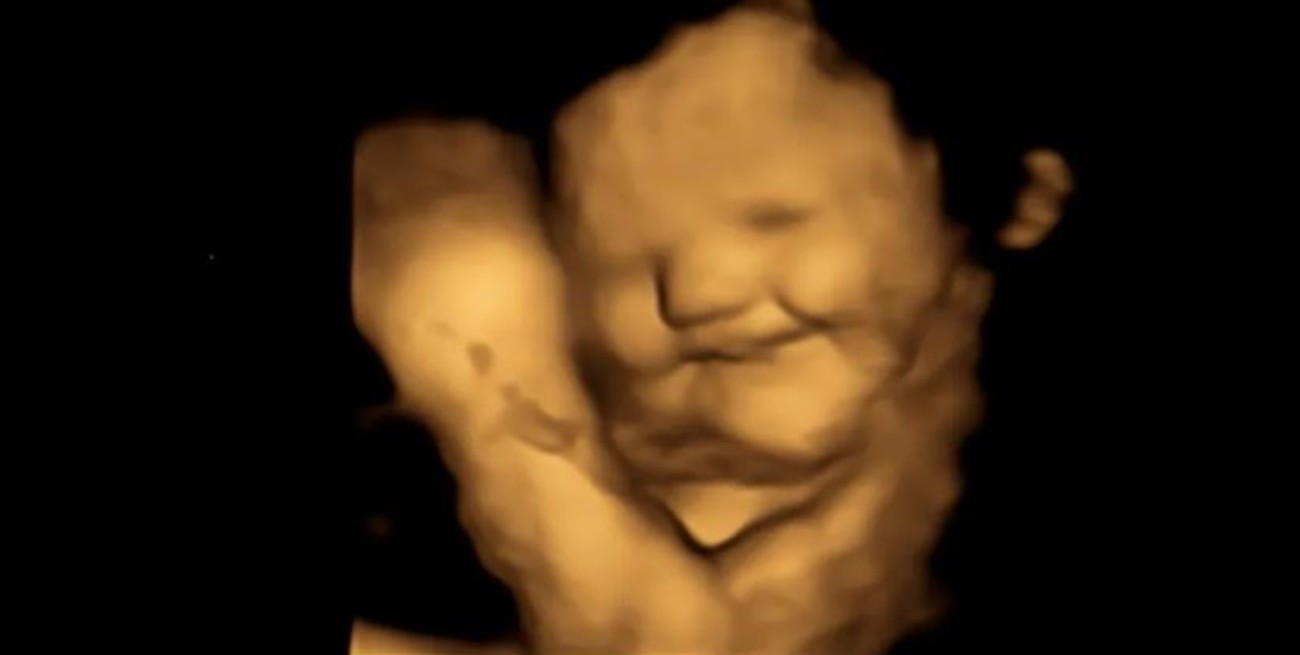

Los fetos crean más "cara de risa" en el útero cuando se exponen al sabor de las zanahorias que consume su madre y crean más "cara de llanto" cuando se exponen al repollo, según un estudio publicado este miércoles en la revista académica Psychological Science.

Los fetos crean más "cara de risa" en el útero cuando se exponen al sabor de las zanahorias que consume su madre y crean más "cara de llanto" cuando se exponen al kale, también conocido como col rizada, según un estudio publicado este miércoles en la revista académica Psychological Science.

Mientras que el sabor de la zanahoria puede ser descrito como "dulce" por los adultos, se eligió el kale porque transmite más amargor a los bebés que otras verduras verdes como las espinacas, el brócoli o los espárragos, según el estudio. Tras un periodo de espera de 20 minutos después del consumo, las mujeres se sometieron a ecografías en 4D, que se compararon con imágenes en 2D de los fetos.

Los tirones de las comisuras de los labios, que sugieren una sonrisa o una risa, fueron significativamente mayores en el grupo de la zanahoria en comparación con el grupo del kale y el grupo de control. Mientras que movimientos como la elevación del labio superior, la caída del labio inferior, la presión de los labios y una combinación de ellos, que sugieren una cara de molestia o llanto, fueron mucho más comunes en el grupo del kale que en los otros grupos.

Los avances tecnológicos han permitido obtener mejores imágenes de los rostros de los fetos en el útero, según la profesora Nadja Reissland, directora del Laboratorio de Investigación Fetal y Neonatal de la Universidad de Durham. Reissland, que supervisó la investigación, desarrolló el Sistema de Movimiento Observable Fetal (FMOS, por sus siglas en inglés), con el que se codificaron las ecografías en 4D.

"A medida que la tecnología avanza, las ecografías son cada vez mejores y más precisas", declaró, y añadió que esto "nos permite codificar los movimientos faciales del feto fotograma a fotograma con todo detalle y a lo largo del tiempo".